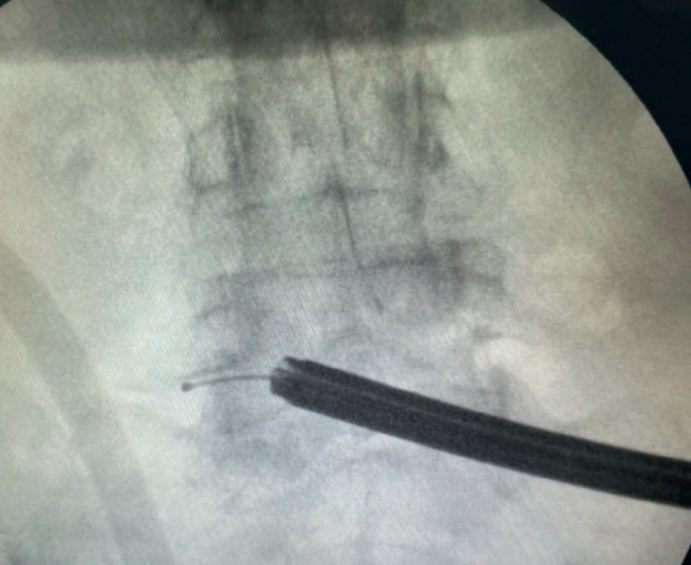

Figure 7. Radiological view of ipsilateral single-portal interlaminar endoscopy. The lateral view shows the trajectory of progression and the depth.